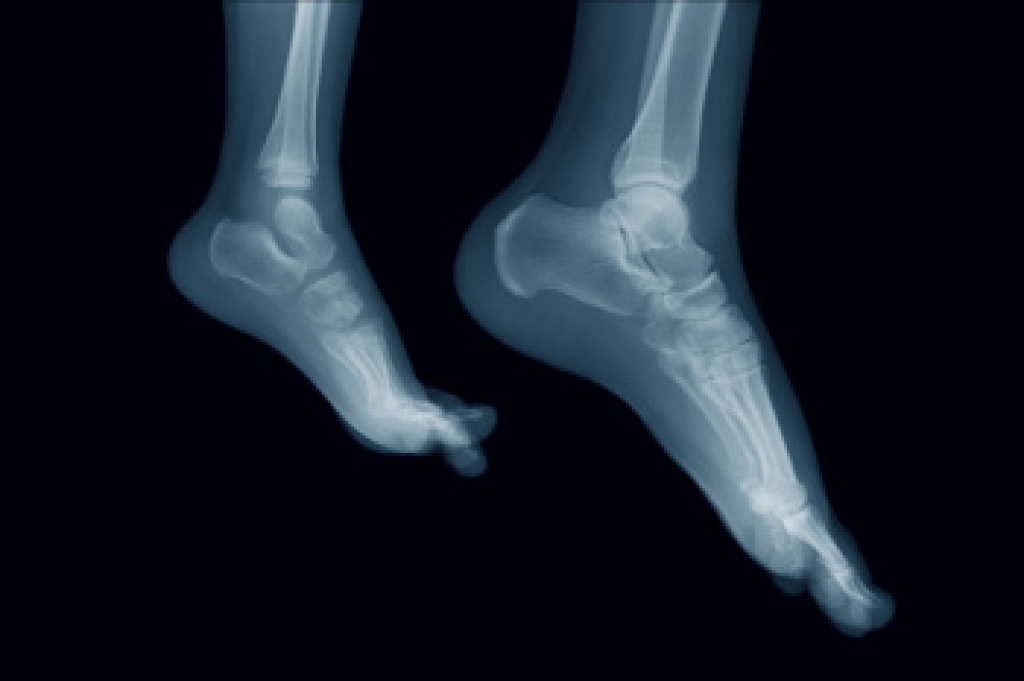

The foot and ankle form a complex structure designed to support body weight, absorb shock, and maintain balance during movement. They consist of numerous bones connected by joints, ligaments, and muscles that work together to provide strength and flexibility. The soles and ankles contain sensory receptors that help the body detect pressure and adjust balance with each step. When any part of this system is injured or strained, it can affect mobility and stability. A podiatrist can assess structural issues, treat injuries, and recommend exercises or custom orthotics to restore proper function. If you have developed foot pain, it is suggested that you consult a podiatrist who can determine the cause and offer effective treatment solutions.

Podiatric biomechanics is a particular sector of specialty podiatry with licensed practitioners who are trained to diagnose and treat conditions affecting the foot, ankle and lower leg. Biomechanics deals with the forces that act against the body, causing an interference with the biological structures. It focuses on the movement of the ankle, the foot and the forces that interact with them.